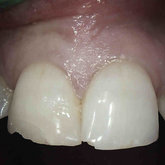

Porcelain crowns and restorations made in one appointment.

We make it a priority to incorporate the latest in dental technology in everything we do at our practice. ...